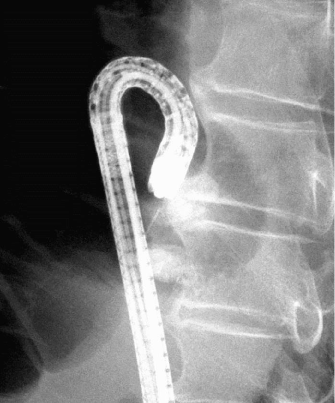

For endoscopic obliterative therapy for gastrointestinal varices, we used n-butyl-2-cyanoacrylate diluted to a final concentration of 70% or 83% (except one case of duodenal varices) in 5% Lipiodol®, (Guerbet Asia Pacific, Tsuen Wan, Hong Kong). Lipiodol® prevents the tissue adhesive from polymerizing too quickly and also allows for radiographic monitoring. Obliterative therapy was performed repeatedly every week with a 23-gauge needle until gastrointestinal varices disappeared. Fluoroscopic observation with an infusion of n-butyl-2-cyanoacrylate (avoiding flow into the systemic circulation) was performed to determine the extent of the varices (Figure 2a and 2b).

Figure 2-b. Fluoroscopic image of endoscopic obliterative therapy